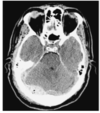

Describe this CT

The arrows show septations within the collection.

There is mass effect causing effacement of the sulci with the right lateral ventricle displaced downwards out of the imaging plane indicating downward brain hernaition.

Little midline shift is evident.